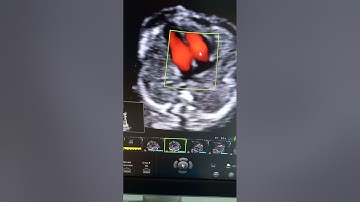

Siêu âm Doppler tim trong cấp cứu